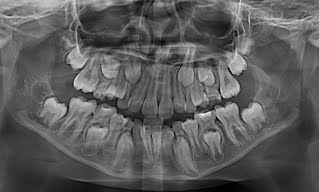

1) पॅनोरमिक एक्स-रे-

यात एकाच एक्स-रे मध्ये आपले वरचे खालचे सर्व दात ,जबडा , जबड्याचा सांधा, वरच्या जबड्याजवळ असणारा सायनस हे सर्व दिसते.

तसेच लहान मुलांच्या बाबतीत तोंडात उगवलेले दात व जबड्यामध्ये नव्याने तयार होणारे दात हे सर्व देखील व्यवस्थित बघता येते